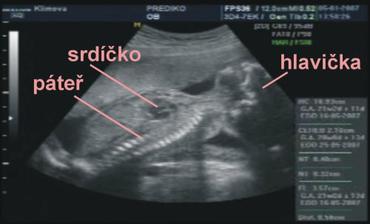

Nedovedete si představit to velké štěstí...které nás potkalo, je to prostě náš ZÁZRAK. Teď jsem sice plná obav a strachu o miminko, i nějaké komplikace se vyskytli, ale snad všechno dobře dopadne, a nám se v květnu, rok po naší svatbě, narodí krásné a zdravé miminko...náš malý - Velký Zázrak.